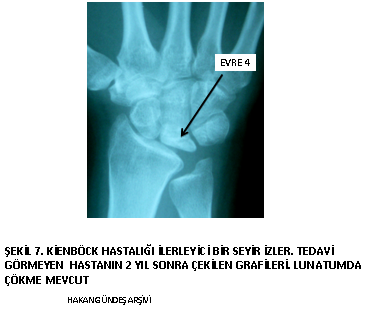

Hastalık radyolojik gözlemlere göre dört evreye ayrılır. Tedavi edilmemesi durumunda ilerleyip ilerlemeyeceği ve ilerlerse kişiyi ne düzeyde etkileyeceğini önceden kestirmek zordur. Yapılan çalışmalarda hastalığın büyük çoğunlukla ilerleyici ve kısıtlayıcı olduğu gözlenmiştir (şekil 6 ve 7).